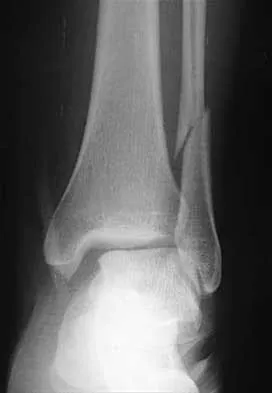

Figures 4a through 4c show the radiographs of a 43-year-old woman who sustained a twisting injury to her right ankle. She has ankle pain and tenderness medially and laterally. To help determine the optimal treatment, an external rotation stress radiograph of the ankle is obtained. This test is designed to evaluate the integrity of what structure?

Explanation

In the presence of a supination external rotation-type fracture of the distal fibula (Weber type B), stability of the ankle is best assessed by performing an external rotation stress AP view of the ankle. This test is used to assess the integrity of the deltoid ligament. The presence of a deltoid ligament rupture results in instability and generally is best managed surgically. The gravity stress test can also be used. Egol KA, Amirtharajah M, Tejwani NC, et al: Ankle stress test for predicting the need for surgical fixation of isolated fibular fractures. J Bone Joint Surg Am 2004;86:2393-2398. McConnell T, Creevy W, Tornetta P III: Stress examination of supination external rotation-type fibular fractures. J Bone Joint Surg Am 2004;86:2171-2178.